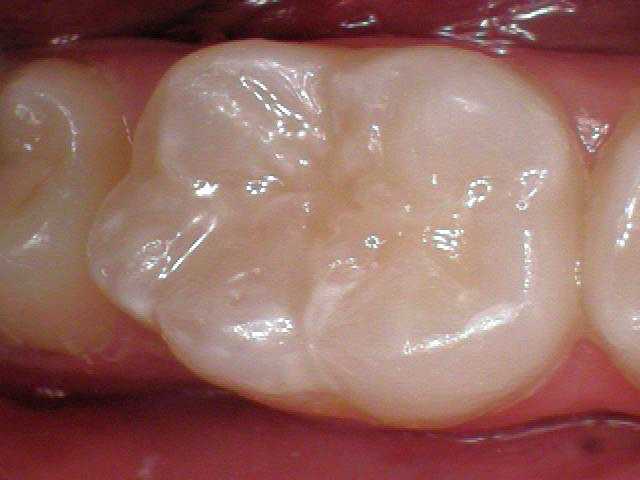

Removing small amount of tooth without needles, drills, or pain

Finished air abrasion filling